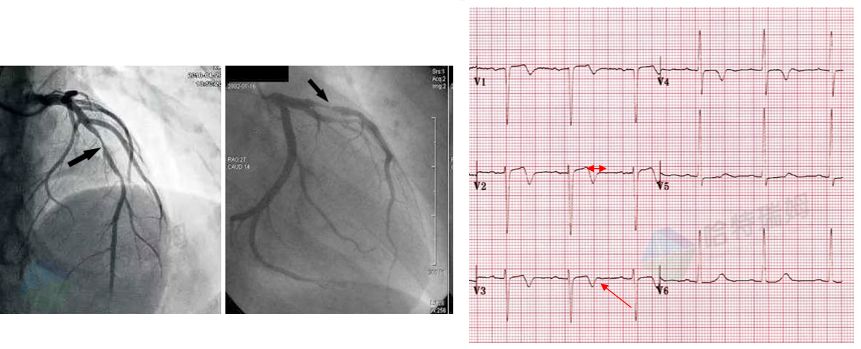

心肌缺血的T波倒置

图3 胸导联(V1~V4)T波倒置经冠脉造影证实,该患者前降支近段有病变。

图4 前降支近段病变vs T波倒置正常情况下,心室复极从心外膜向心内膜进行,当心外膜下心肌缺血时,心室肌的复极由心内膜向心外膜方向,与正常复极过程相反,因此,心电图上表现为T波倒置。

缺血性T波(也称冠状T波)的心电图特点:双支对称、底部变窄、顶端变尖,T波与ST段有明确的分界点。

Wellens综合征的T波改变

图5 Wellens综合征的T波改变Wellens综合征了解一下~

1982年, Wellens等人提出Wellens现象,即前降支近段狭窄患者存在特征性T波改变,此后,人们将其命名为Wellens综合征,其图形有2种形态。

以上两种T波改变可以在同一患者不同时间段出现,T波形态也随疼痛性质动态改变。

Wellens综合征:

前降支近端狭窄患者存在特征性T波改变。

A型Wellens综合征:

主要为V2~V3导联,T波呈正负双向。

B型Wellens综合征:

ST位于等电位线,或呈直线型或拱形轻度抬高(<1 mm),紧接对称性倒置T波。

T波形态可在A、B型之间动态改变,疼痛最剧烈时T波最高,缓解时T波双向,后出现T波倒置。